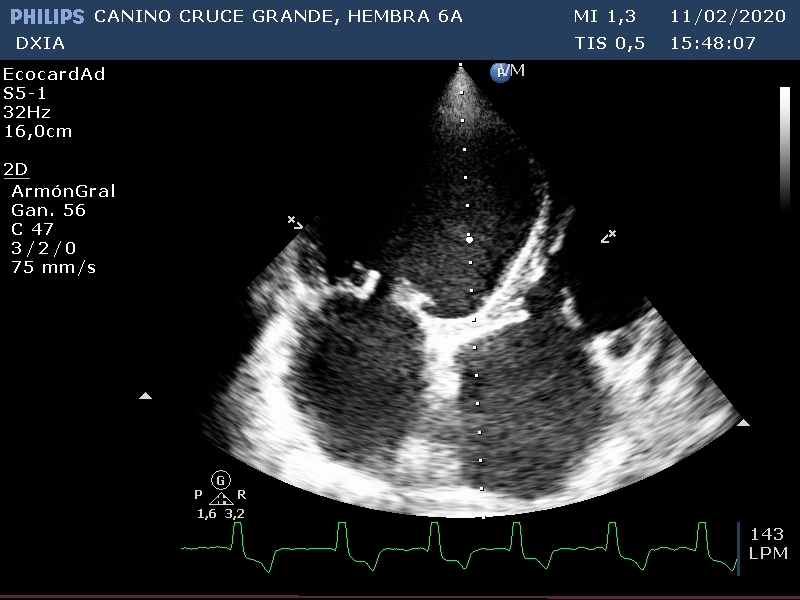

Comentario respecto al estudio ecocardiográfico:

- Derrame pericárdico sin taponamiento cardiaco.

- Marcada dilatación de cámaras cardiacas.

- Engrosamiento nodular de la VM compatible con posible enfermedad degenerativa.

- Flujo regurgitante mitrálico y tricuspídeo.

- FA, SSPVE, IE compatible con CMD.

- ECG: Fibrilación atrial de base con presencia de CPVs aislados.

CONCLUSIÓN:

La paciente presenta CMD con cambios nodulares en las valvas de la VM ¿CMD Y/O DVM?